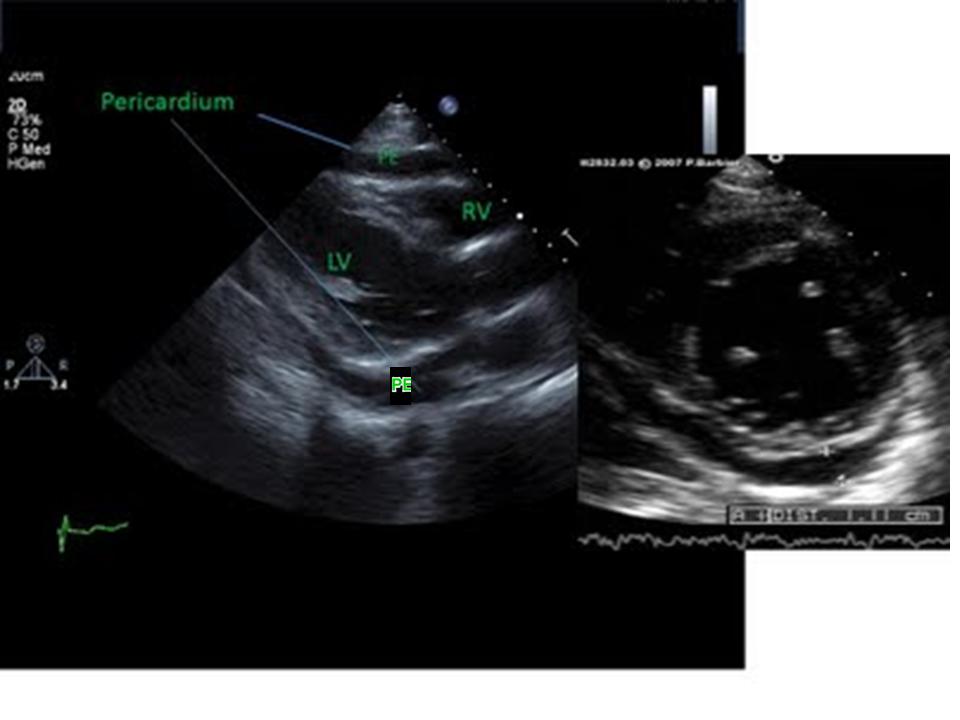

Το υπερηχογράφημα καρδιάς είναι η απόλυτη διαγνωστική εξέταση αφού αναδεικνύει την ύπαρξη υγρού στο περικάρδιο, αλλά και την λειτουργικότητα της καρδιάς. Η μαγνητική τομογραφία καρδιάς τέλος δίνει απαντήσεις για τις εντοπισμένες συλλογές στο περικάρδιο και την επίπτωσή τους στην καρδιακή λειτουργία.